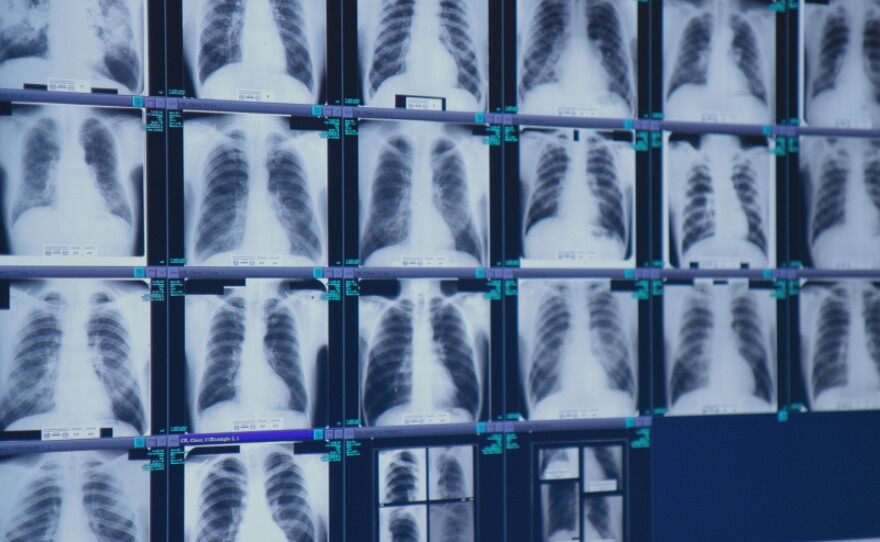

Dr. Brandon Crum reviews X-rays of coal miners with severe black lung disease at his clinic in Pikeville, Ky.

"As of now, we are almost at 700 cases of complicated black lung," said Dr. Brandon Crum, a radiologist specializing in black lung X-ray assessments at United Medical Group in Pikeville, Ky.

"I'm surprised that we continue to see that much disease and the severity of the disease," Crum added. "We're seeing younger and younger miners get it. ... Men in their 30s, 40s and 50s on a regular basis."